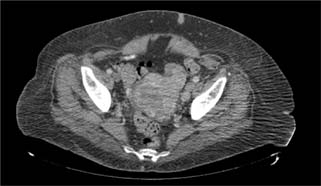

Microscopic examination revealed a tumor composed of nests of clear cells surrounded by interconnecting vascular framework. Cells with eosinophilic cytoplasm were also noted in combination with the clear cells. Immunohistochemical stains, including vimentin, were positive, and CD10 showed diffuse membranous positivity. Eosinophilic nucleoli were identifiable at 100×, consistent with Grade 3 tumor using the International Society of Urological Pathology (ISUP)/WHO grading scheme (13). No sarcomatoid or rhabdoid areas were noted. These findings rendered a diagnosis of left kidney clear cell RCC, which extended into the renal vein, left ovarian vein and uterus, left fallopian tube, and bilateral ovaries (Figure 4). The final pathologic stage was pT4N1M1.

Figure 4: Microscopic evaluation of the tumor revealed nests of clear cells surrounded by interconnecting vascular framework, consistent with the ultimate diagnosis of clear cell renal cell carcinoma.